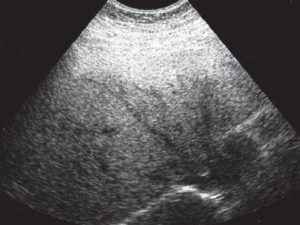

Диагноз в случае стеатоза ставится на основе инструментальных методов исследования — УЗИ печени, биохимического анализа крови. На УЗИ печень имеет «пестрый» вид за счет неравномерной структуры заполненных жирами гепатоцитов, а в анализах крови повышаются печеночные ферменты (АСАТ, АЛАТ), а также липиды крови, что отражает тесную связь между нарушением липидного обмена и стеатозом.

УЗИ печени позволяет выявить морфологические и структурные изменения органа, такие как:

- Гиперэхогенность – уплотнение тканей.

- Гепатомегалию – увеличение размеров печени.

- Жировую инфильтрацию – скопление веществ, которые в норме отсутствуют.

- Неоднородность плотности органа.

Признаки жирового гепатоза на УЗИ

При УЗИ могут быть выявлены следующие эхопризнаки гепатоза:

- уплотнение тканей печени

- увеличение размеров органа и его выход за края подреберной области

- жировое перерождение тканей печени

- неоднородность распространения поврежденных участков по органу.

УЗИ-признаки жирового гепатоза печени

Выделяют диффузную, локальную, очаговую и периферическую формы жировой инфильтрации, которые отличаются лишь распространением поражения. При диффузной форме размеры печени умеренно увеличиваются, но форма при этом не меняется.

Ультразвуковое исследование показывает снижение звукопроводимости органа, которое проявляется неотчетливой визуализацией глубоких отделов печени и диафрагмы и ухудшением визуализации мелких ветвей венозного рисунка.

При локальной форме жировой инфильтрации наряду с пораженными участками встречаются участки печени с неизменной паренхимой. Эти сохраненные участки печени при УЗИ проявляются фрагментами пониженного отражения звука на фоне общего снижения звукопроводимости от пораженной паренхимы.